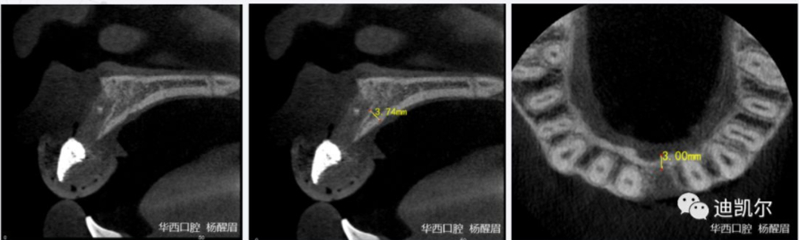

術(shù)前CBCT圖像和測量數(shù)據(jù)

*早期種植病例,頰側(cè)組織凹陷,肉眼可見骨缺損,需要種植同期GBR

*CBCT顯示骨缺損嚴重,種植窩洞制備困難,種植體很難獲得初期穩(wěn)定性